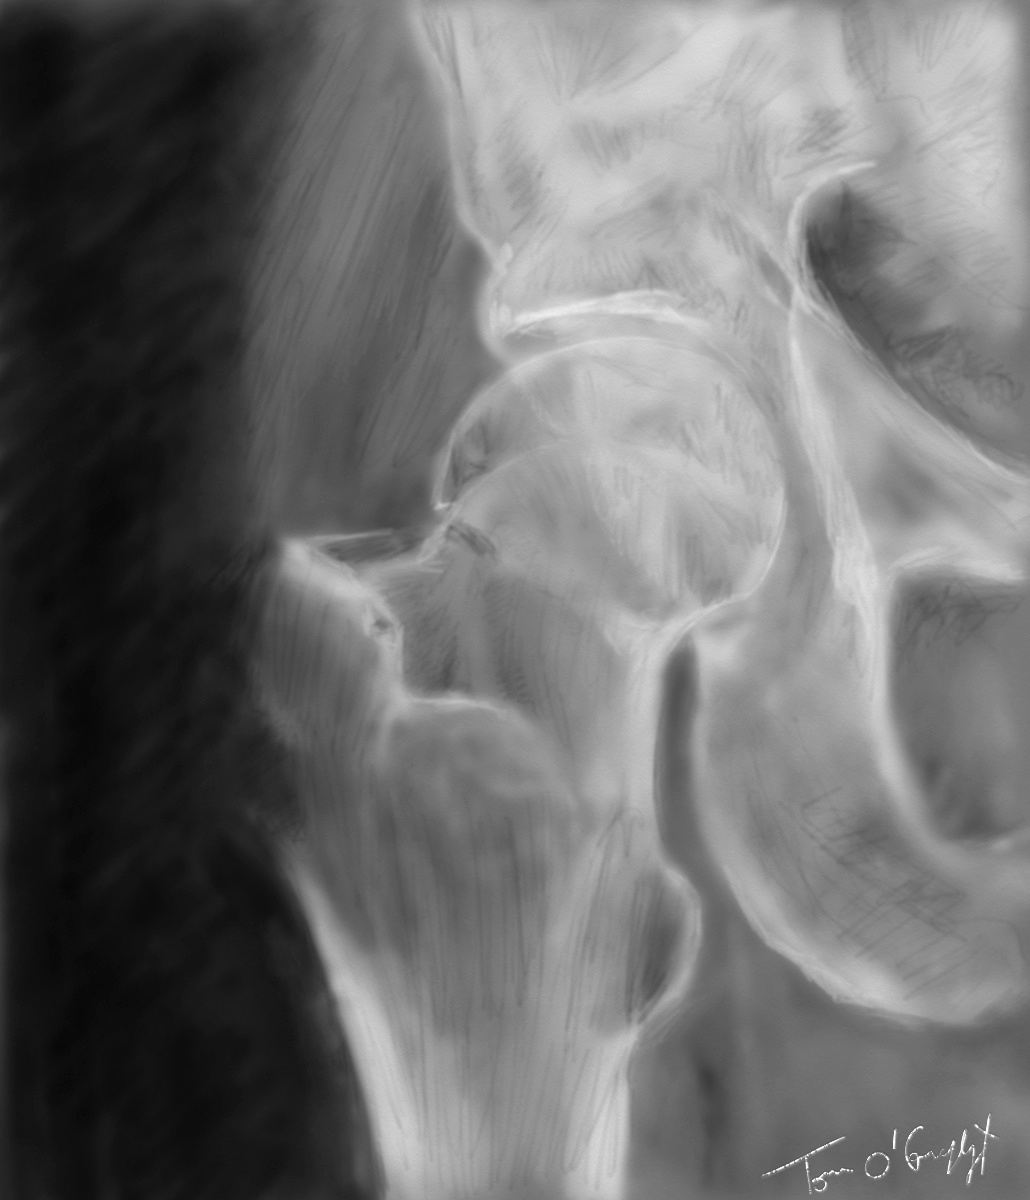

fracture col femur radiographie

fracture du col du fémur type 1 de Garden, déplacement en valgus de la tête fémorale

La plus utilisée est la classification de Garden même si elle n’interprète le déplacement que sur le plan frontal.

1. Fracture incomplète, de la corticale supérieure sans atteinte théorique de l’inférieure. La tête se déplace en valgus, en se redressant. C’est le prototype de la fracture engrenée stable.